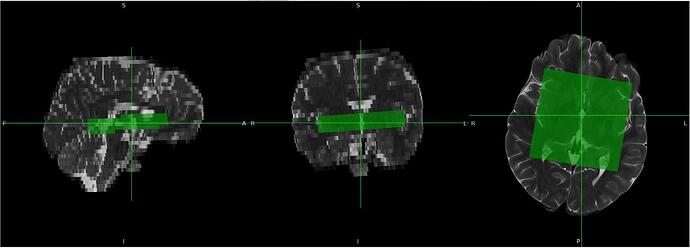

Last week, I tried several approaches to derive orientation values, and I think I have found a method to overcome this issue. Instead of using the SlabOrientation values, I derived rotation angles (in radians) from the RowVector and ColumnVector matrices by decomposing them into Euler angles. I tested this approach on multiple datasets, and so far it appears to work well.

For voxel positioning, I used the MidSlabPosition matrix instead of PositionVector. Apart from these changes, I did not make any major modifications to the existing code.